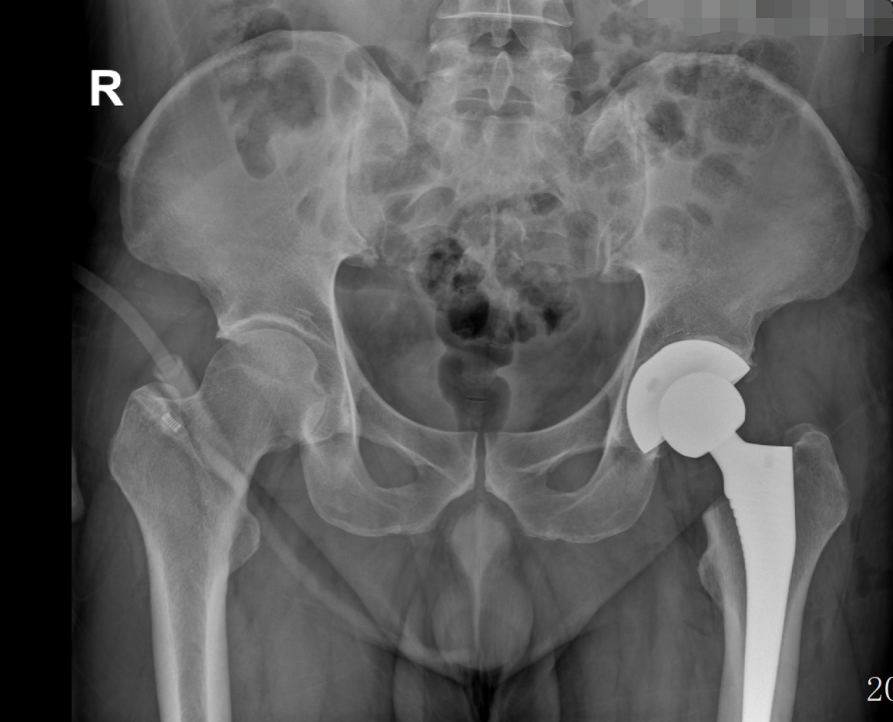

近日,我院骨科在南方医科大学第三附属医院(以下简称“南医三院”)派驻专家、学科带头人胡舒主任的带领下,为一名43岁的壮年患者吴先生(化名)实施左侧全髋关节置换术。

经胡舒主任详细检查,吴先生确诊为左侧股骨头缺血性坏死(三期)。由于保守治疗效果不佳,为有效改善功能、缓解症状,胡舒主任建议进行全髋关节置换。在充分沟通和了解了自己的疾病及治疗方式后,吴先生选择在家门口的东凤人民医院手术治疗,方便了家人护理和后续自己的定期复诊。

术前(骨盆正位)                                                                                                                           术后(骨盆正位)

术后快速恢复,术后次日,重拾步伐

得益于南医三院专家团队的手术技术以及贯穿围手术期的ERAS管理流程,吴先生的手术及康复过程非常顺利:

▪️术后第1天:在医护人员的协助下,顺利下床站立,并使用助行器完成行走;

▪️术后第3天:已不需要借助助行器便可以自由行走。